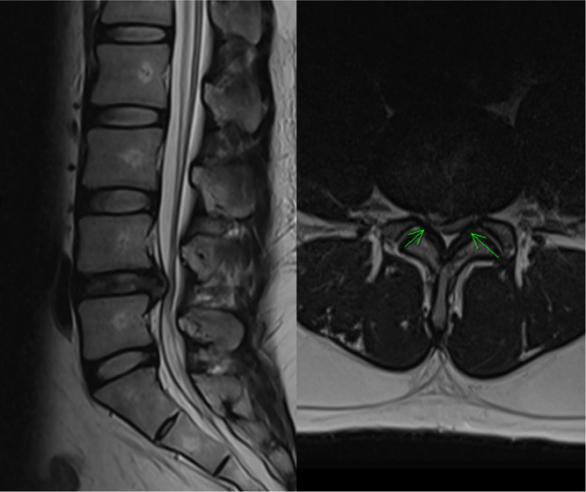

患者是一位32岁的年轻男性,因持续三个月的腰痛,并伴有右下肢麻木和放射痛前来就诊。磁共振成像(MRI)显示L4-L5水平存在副中间型椎间盘突出(图1:MRI)。患者三年的高血压病史控制良好,血压一直保持在120/70 mmHg,没有使用抗凝剂的病史,也没有任何已知的眼部或全身疾病。

图1 术前腰椎MRI(T2加权图像)。左:矢状面图像显示L4-L5水平椎间盘突出压迫硬膜囊。右:L4-L5水平的轴向图像